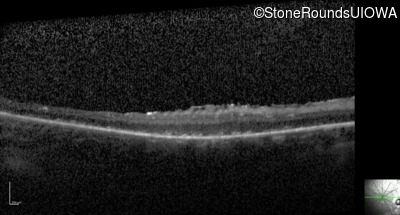

Optical Coherence Tomography - Left - 5/140 sc

Exemplar / OCT Stack

OCT Stack